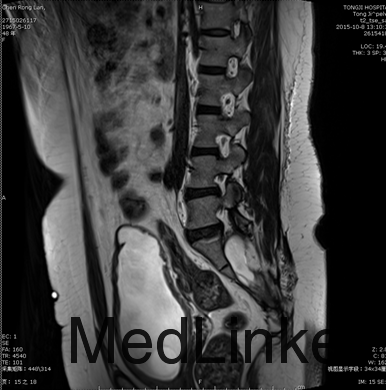

查体:体温36.4℃脉搏80次/分(规则)呼吸19次/分(规则),血压138/80mmHg,双肾区无叩击痛,双下肢无水肿,外生殖器无见明显异常。 辅助检查:2015-10-03尿常规:红细胞(隐血)1+ 白细胞(粒)1+尿蛋白2+白细胞计数45.0/ul; 2015-09-30彩超示:左肾体积缩小,尿潴留。发病以来精神尚可,小便如上述,大便干燥,体重无明显改变。 尿动力学检查示:膀胱收缩乏力(神经源性);膀胱感觉迟钝,残余尿增多;建议行间歇导尿治疗。 骶丛神经MRI平扫及功能成像:1、盲囊囊性扩张, 骶尾骨发育不良;2、脊髓圆锥下移(S1下缘水平),脊髓栓系可;3、右侧S3、4神经根显示欠清,右侧S2、左侧S2、3、4神经根显示纤细;4、宫颈纳氏腺囊肿;5、膀胱异常改变,考虑为神经源性膀胱;6、L4/5、L5/S1椎间盘膨出,双侧L4、5神经根受推移。